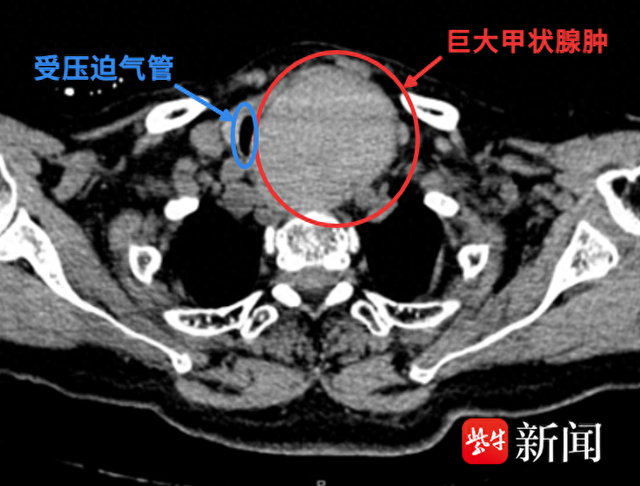

甲状腺肿物俗称“大脖子”病,可9厘米的肿物把气管严重挤压变形,最狭窄的地方就只剩一根筷子头那么细的缝(约3-4毫米),这个罕见的病例在南京医科大学附属无锡人民医院甲状腺外科得到了救治。

这2年,王阿婆脖子上长了个大包块,近几天突然变大,还疼得厉害,连喘气都费劲。因为她年事已高,还患有严重高血压和颅内巨大动脉瘤,当地医院都认为手术风险太大,建议保守治疗。想要进一步治疗的王阿婆辗转找到了南京医科大学附属无锡人民医院甲状腺外科。CT检查显示,王阿婆左边脖子里的甲状腺肿块,竟然达到9厘米×8厘米×6厘米。这个巨大的肿块把王阿婆的气管严重挤压变形,最狭窄的地方就只剩一根筷子头那么细的缝(约3-4毫米),患者随时都有可能窒息。再加上脑袋里那个“不定时炸弹”,情况十分凶险。